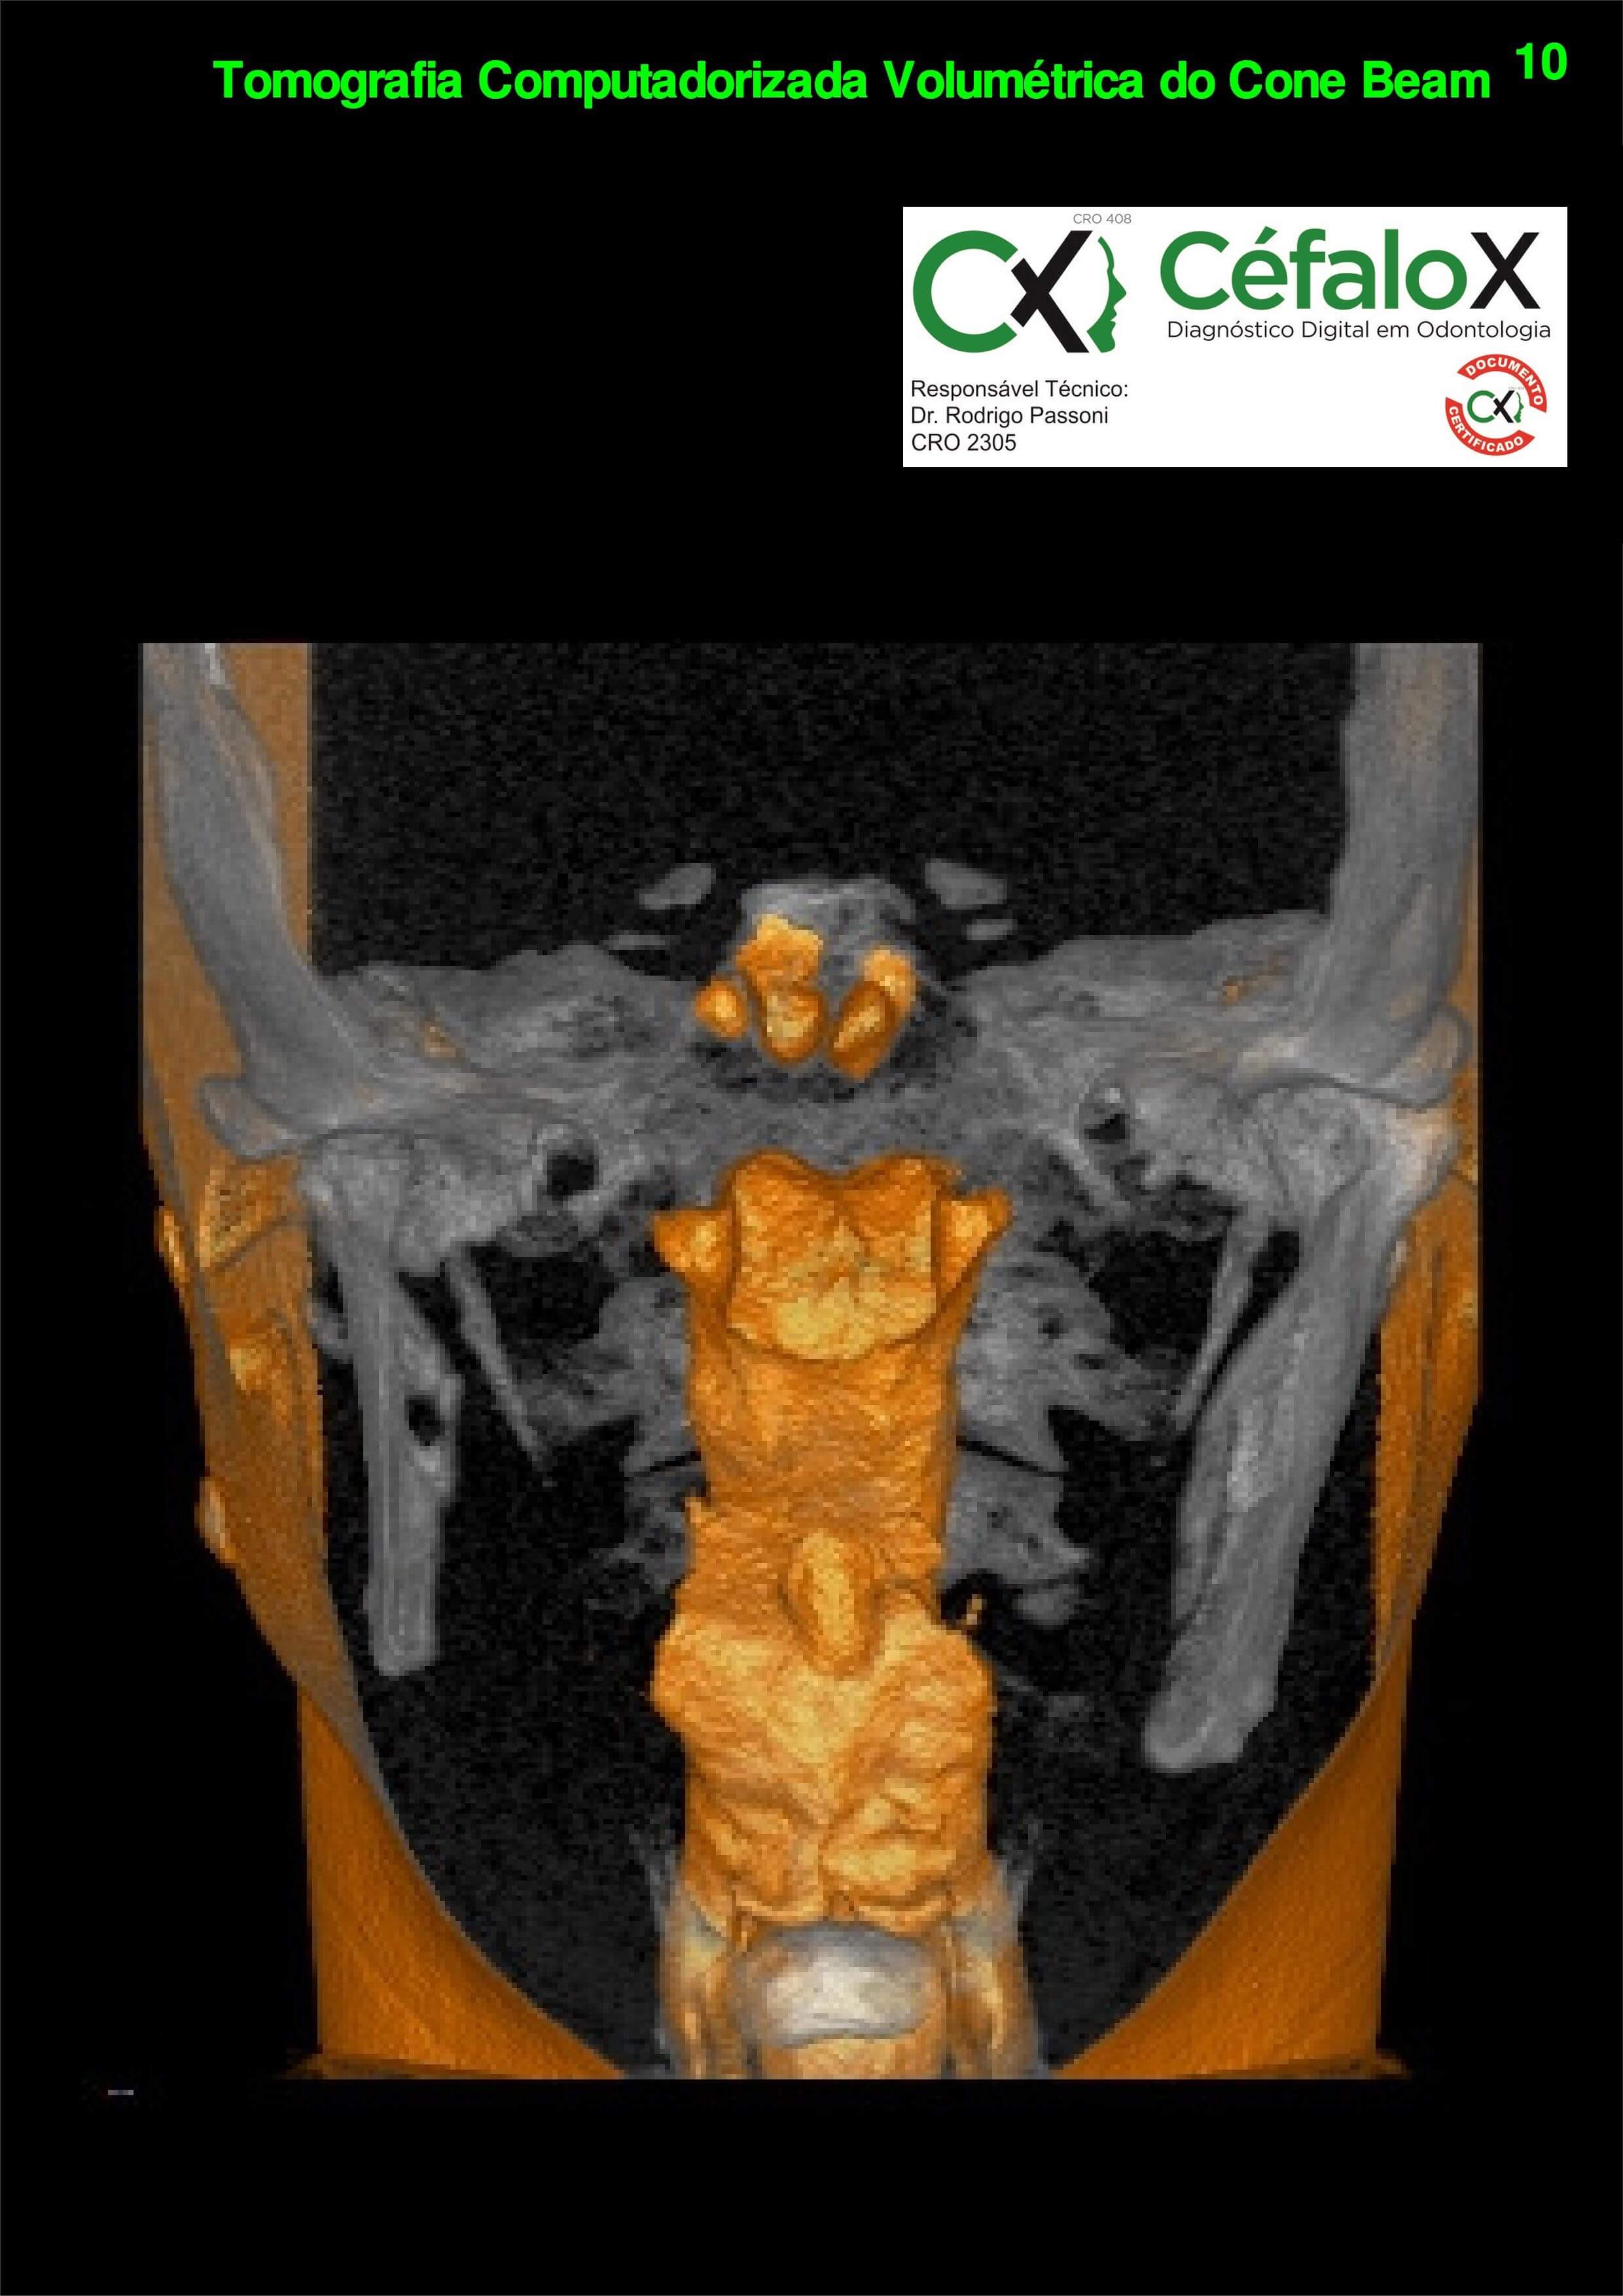

TC de face (do Hióide à Glabela), reconstrução 3D do tecido ósseo, radiografia panorâmica, telerradiografia lateral com traçado, cortes transversais e axial de maxila e mandíbula e arquivo DICOM- entregue em pasta de Pvc.

TC de face (do Hióide à Glabela), reconstrução 3D do tecido ósseo, radiografia panorâmica, telerradiografia lateral e frontal com traçado, cortes transversais e axial de maxila/mandíbula e arquivo DICOM – entregue em pasta de Pvc.

TC de face (do Hióide à Glabela), reconstruções 3D do tecido mole/ósseo/vias aéreas, radiografia panorâmica, telerradiografia lateral e frontal com traçado, cortes transversais e axial de maxila/mandíbula, ATM e arquivo DICOM – entregue em pasta e caixa de Pvc.